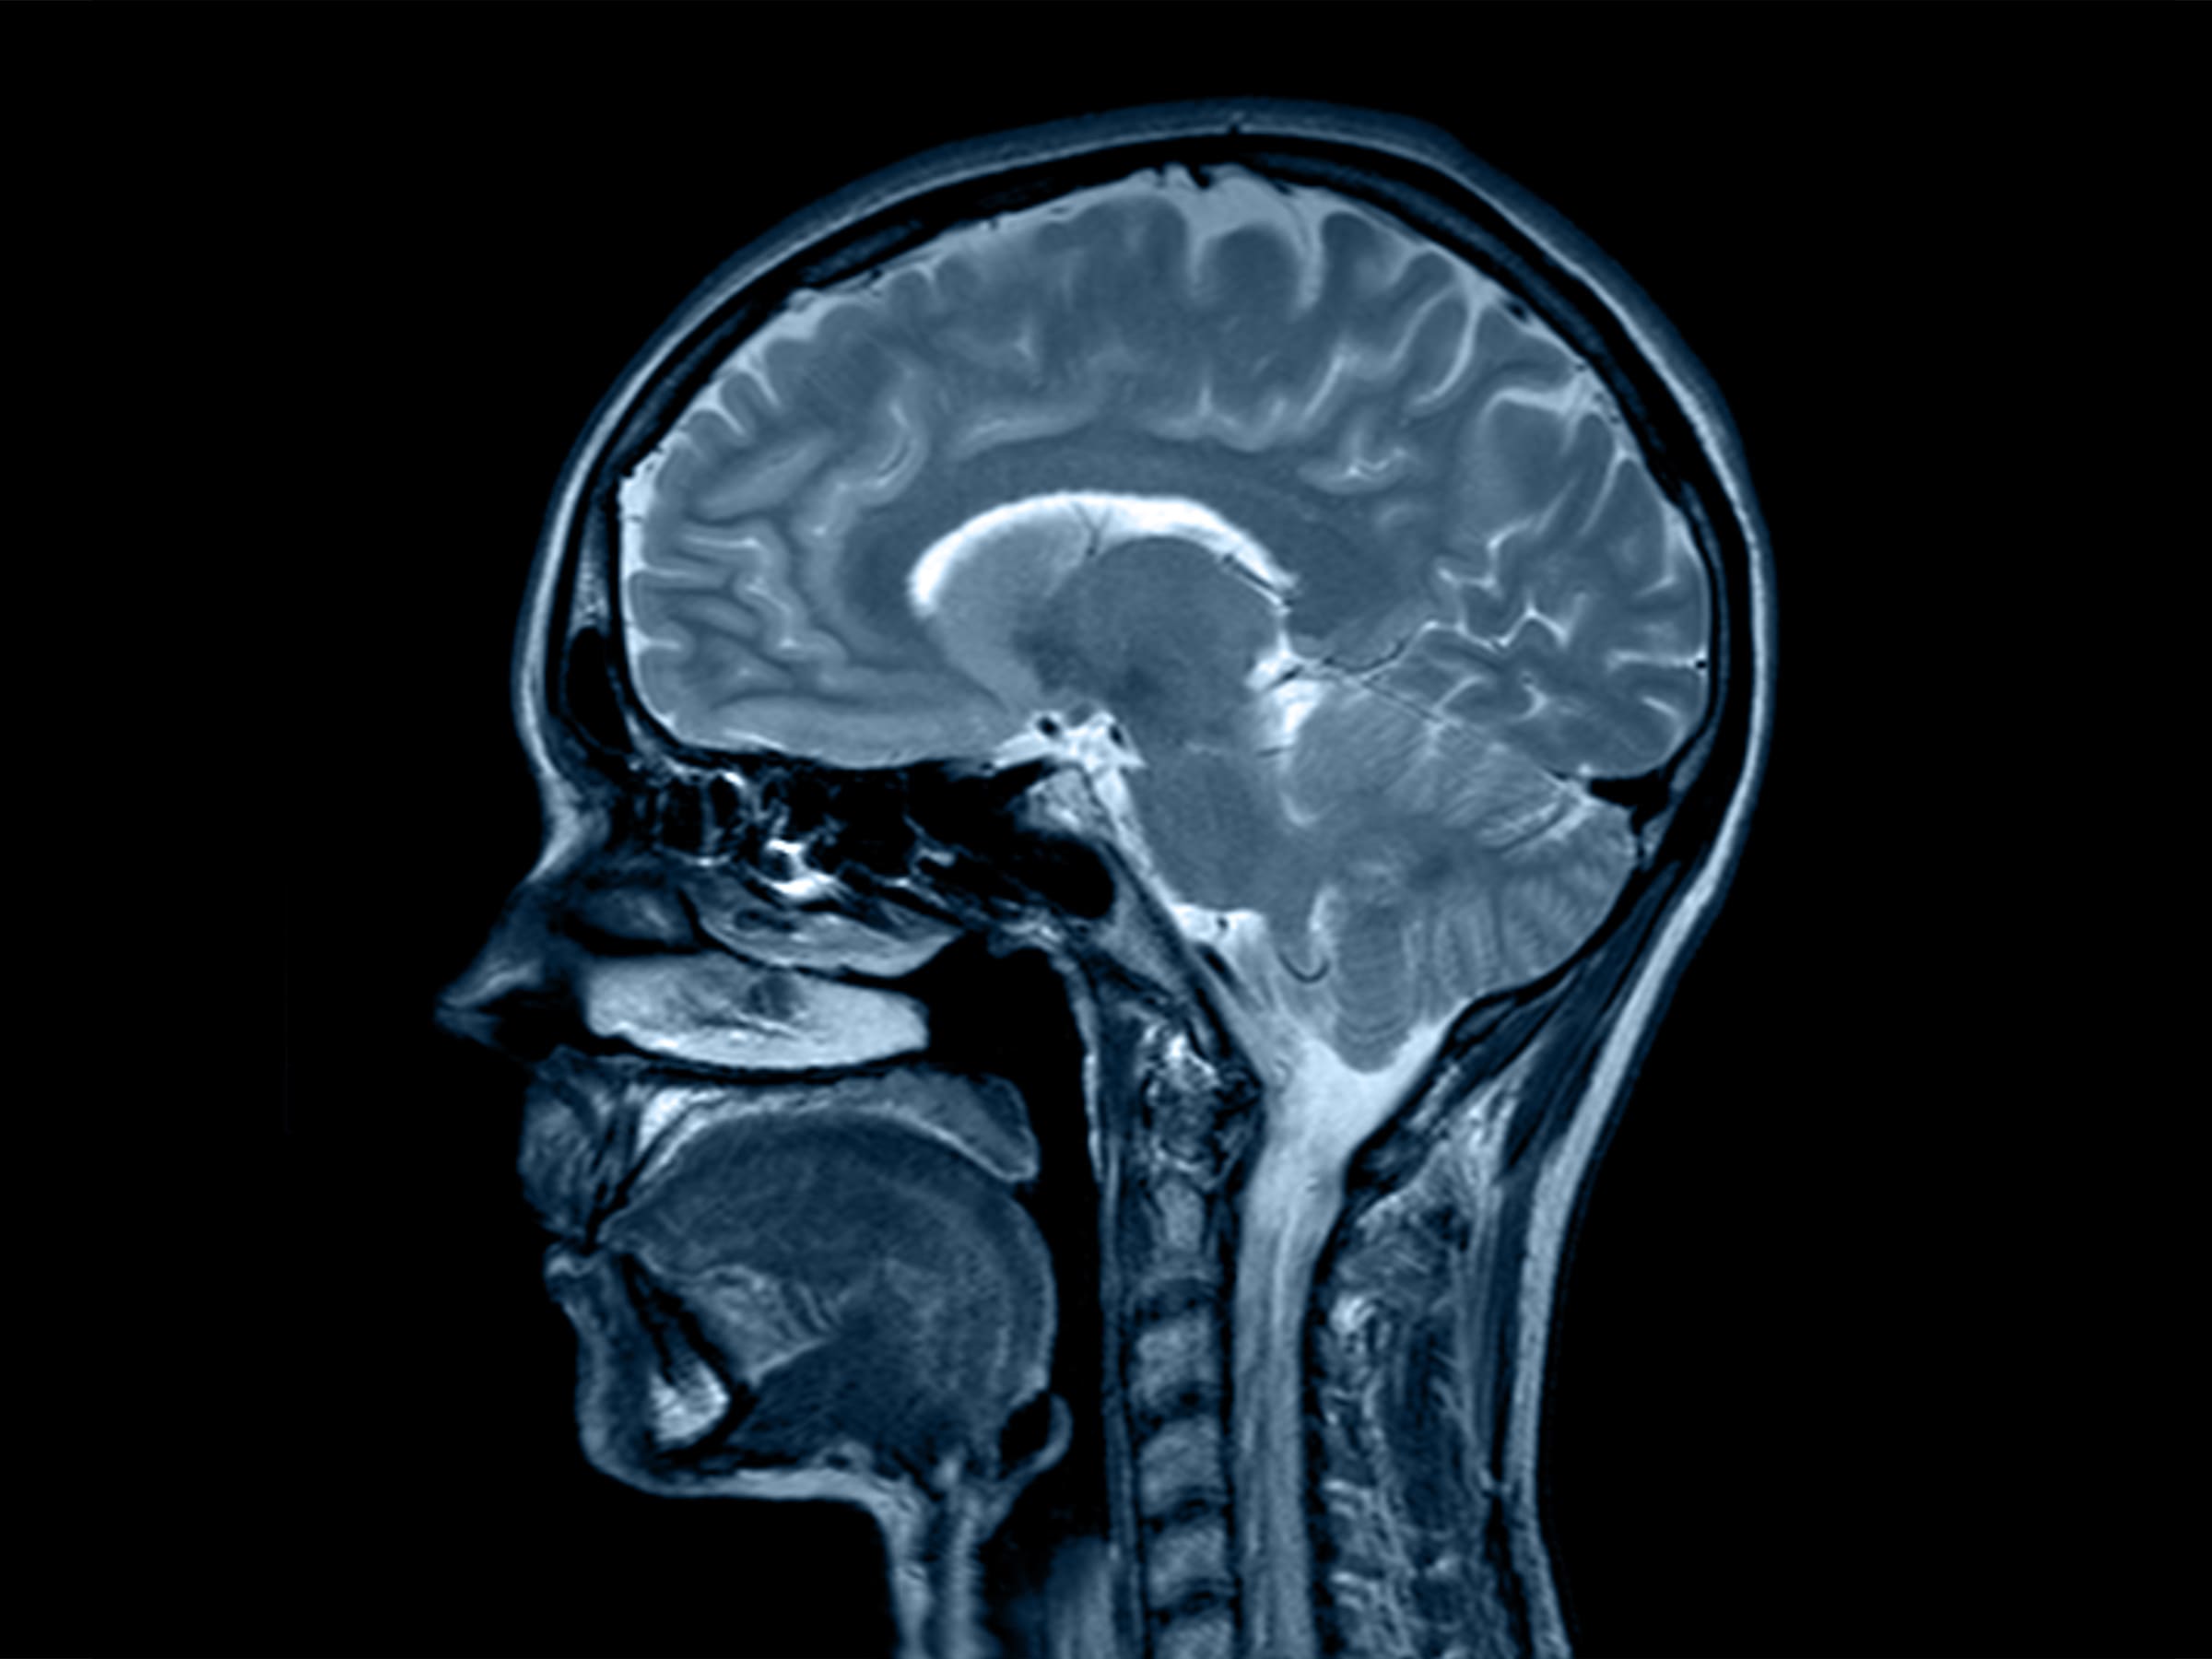

ARNOLD CHIARI MALFORMATION

WHAT IS ARNOLD CHIARI MALFORMATION?

Arnold Chiari Malformation is when parts of the brain protrude into the spinal canal, leading to various neurological symptoms.